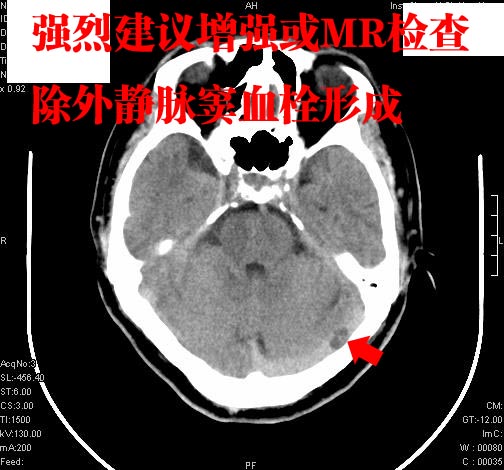

标题: CT9540:M,58岁,左侧横窦低密度影 [打印本页]

患者,58岁,肢体无力,大家看看,除了脑梗塞,左侧横窦低密度影怎么解释。

横窦低密影建议增强或最好用mri后下定义

可能为部分容积效应所致,建议薄层或增强扫描进一步检查。